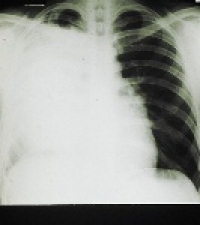

An astounding lack of public awareness about lung cancer has been revealed in a Cancer Research UK study, published.

When almost 1500 people were asked to list possible warning signs of the disease that is the most common cause of cancer death - only 77 people (five per cent) mentioned a cough that doesn’t go away.

Sara Hiom, Cancer Research UK’s director of information and an author of the study published in the journal Thorax, said: “It’s very worrying to see from our survey results that when asked to think of lung cancer symptoms many common ones simply don’t come to mind for most people. A diagnosis of lung cancer is devastating, but if the disease is caught in its earliest stages treatment can improve survival.